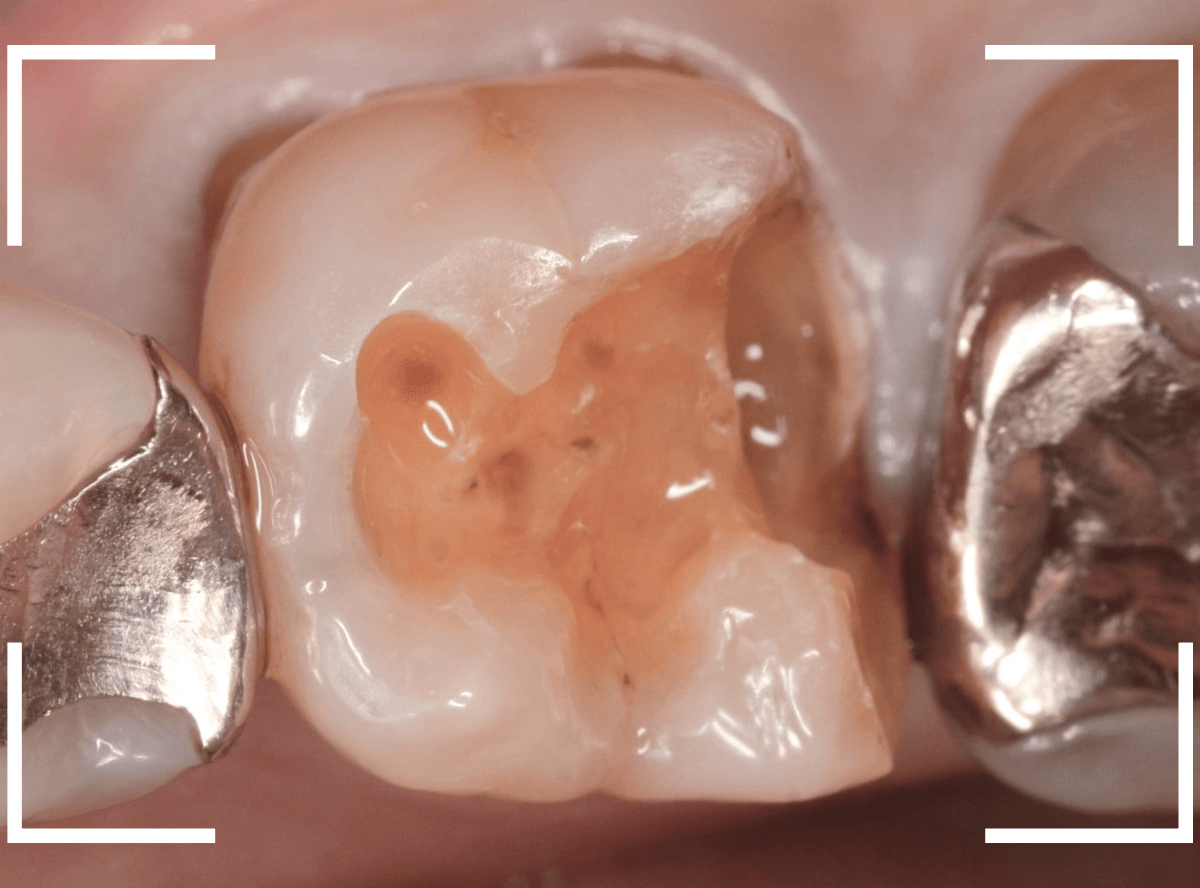

セラミックが精密にsetできるように、歯をトリミングします。

模型上で精密に製作します。

治療後の状態です。

ジルコニア・インレーはE-MAX・インレーより審美性に劣るのですが、患者さんにもご満足いただける仕上がりになり、ホッとしました。